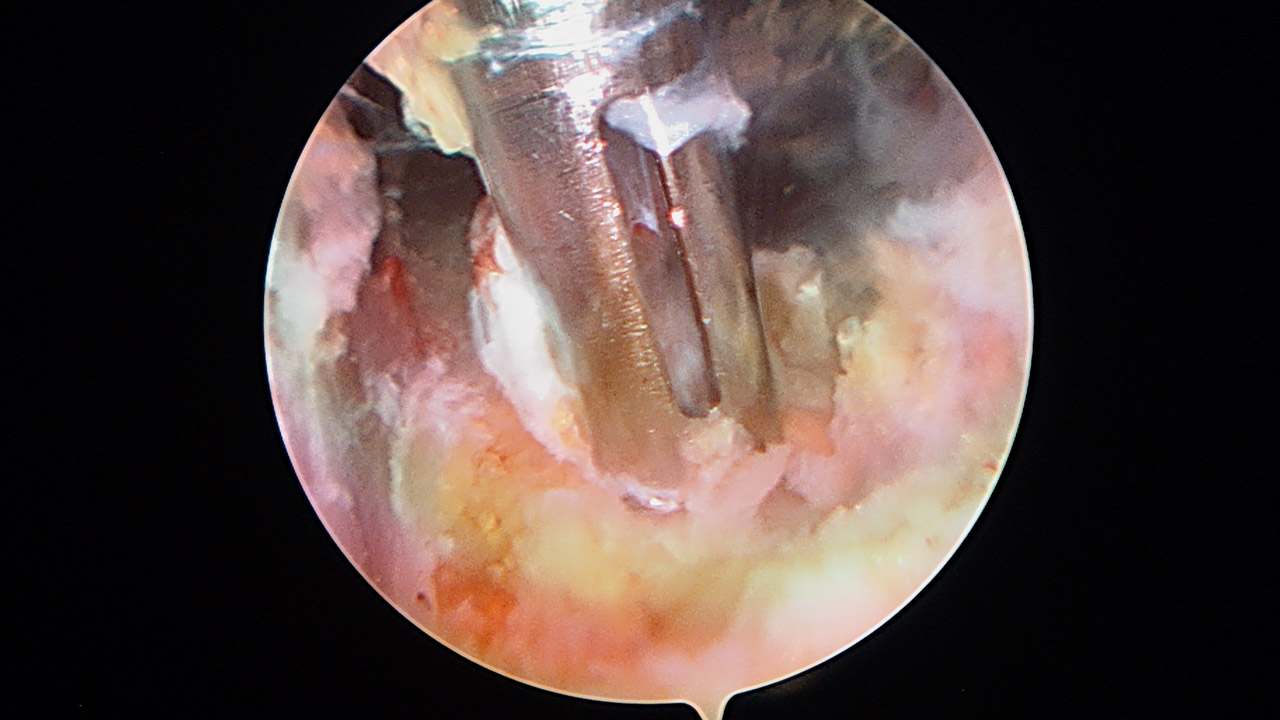

Paso 5: injerto

Para realizar la cirugía se usa un aloinjerto de tibial anterior, con una longitud de 10 cm y un grosor de 7 mm. Se introduce el injerto en el húmero fijándolo con un tornillo interferencial de 7 × 23 (Stryker, Kalamazoo, Mi) (Figura 9). Posteriormente, a través del split, se introduce en el orificio glenoideo, con fijación interferencial 7 × 23 (Stryker, Kalamazoo, Mi) (Figura 10). El injerto reproduce el LGHI, con dirección superior a través del subescapular, y se fija a 45° de rotación externa y 45° de abducción (Figura 11).